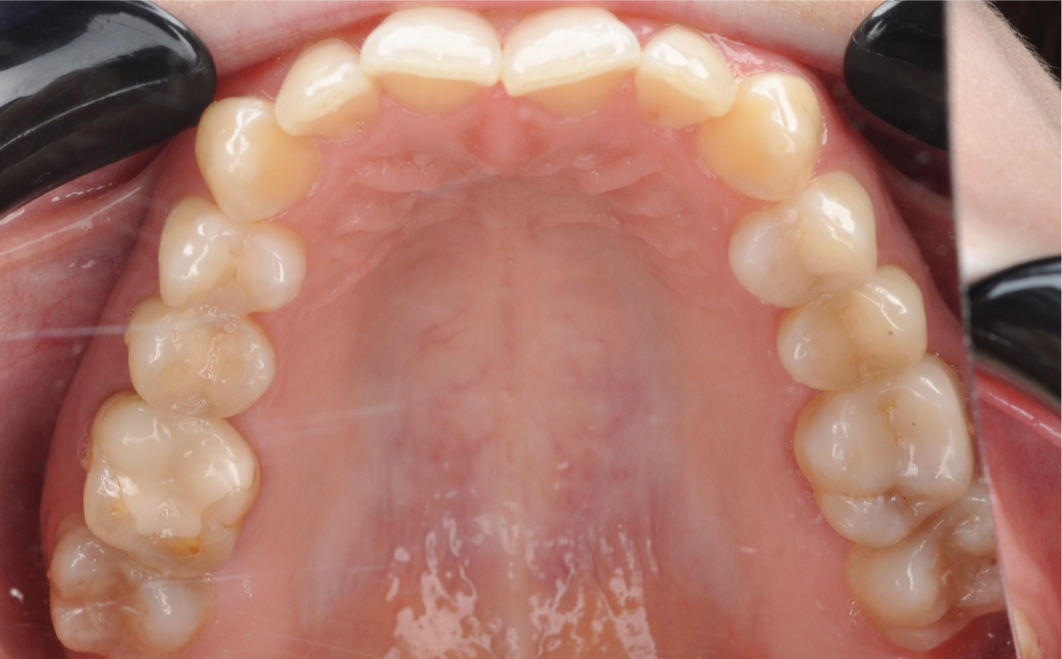

До

Исходная ситуация

Пациентка обратилась в центр комплексной стоматологии «Архитектор Улыбок» с комплексной жалобой, которая затрагивала не только эстетику, но и здоровье всей зубочелюстной системы в целом.

Проблемы с височно-нижнечелюстным суставом (ВНЧС). Пациентка испытывала выраженный дискомфорт в суставной области.

Наблюдались сложности и боль в процессе жевания, что существенно снижало качество жизни.

Помимо физического дискомфорта, пациентку не устраивала эстетика улыбки. В частности, форма и положение зубов.